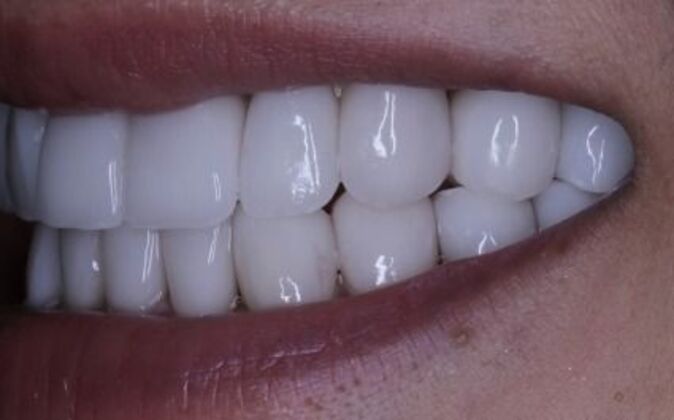

Full Mouth Reconstruction: Risa

Description

Full mouth reconstruction. When you see a client at a young age with so much dental work to begin with you consider your options carefully. You need to be aggressive in approach and conservative in maintaining as much of the healthy tooth structure. Have to consider the age of a patient whenever you embark on a major dental work especially when it involves redoing everything, repositioning and re-establishing a brand new bite position and correcting the inflammatory gum response from previous dental work. You cannot approach a case like this with a limited treatment plan that only addresses a few teeth. If this case is treated one tooth at a time you may leave the patient a “dental cripple”. By that I mean that this patient will constantly be at dental offices for the rest of her life addressing one broken down tooth after another until a cascading domino effect will render all the teeth in a hopeless condition. Here is a situation where we are dealing with multiple problems 1-bite collapse and malfunction 2-gum disease exacerbated by poorly fitting crowns 3-decaying teeth affecting the health of the roots This case had to consider all of these issues. Must understand that this patient is very young and has many years ahead of her so the dentistry has to be done meticulously, conservatively,aggressively and expeditiously. It’s a tough balancing act but as dentists we need to be realistic about our treatment objectives and have a proper plan that addresses dental breakdown. We were able to achieve the esthetic and functional concerns of the patient. Although we felt the color of the teeth were too bright. We do need to consider patients desires since they need to live with this for the rest of their lives and ultimately they need to be happy